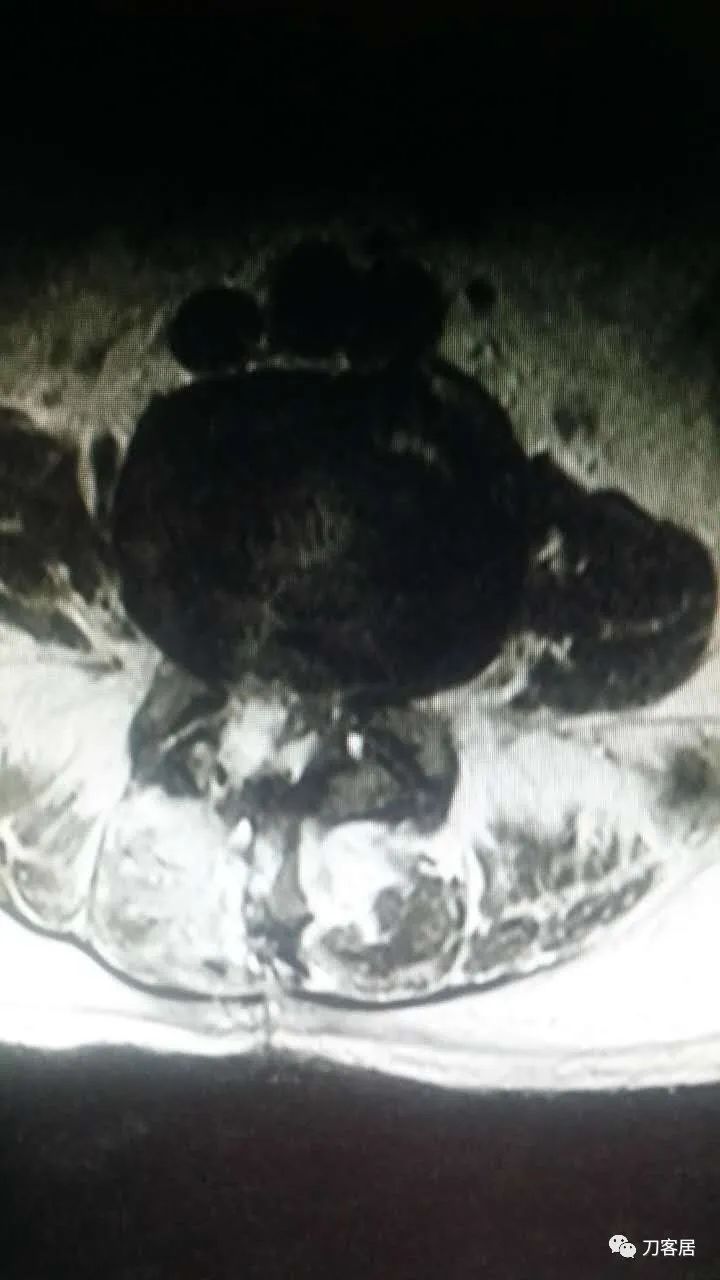

加注图10: 腰1-2椎管内后方可见梭形占位信号改变。

加注图11. 腰1-2椎管内后方可见梭形占位信号改变。

好像是,上面有血肿。